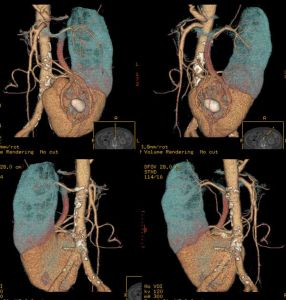

CT掃描可清晰地描繪出腎臟的輪廓,但並非必不可少。對於盆腔融合腎或位於脅腹部者,插入輸尿管導管的平片將為診斷提供第一條線索。逆行造影將顯示腎盂的位置及因有感染或梗阻所致改變。腎閃爍攝影術可顯示出腎塊及其輪廓,如同超聲影象一般。